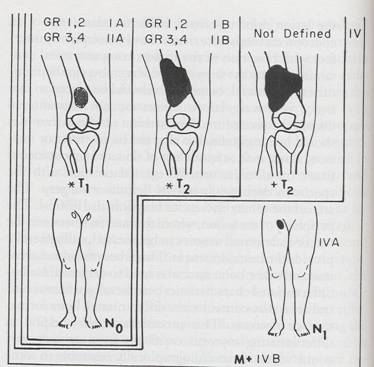

TO: Stadializare

SPM: Stadializare

- T

: T1 vs T2 = <5 vs >5 cm

- N : N0 vs N1

SPM:

Stadializare